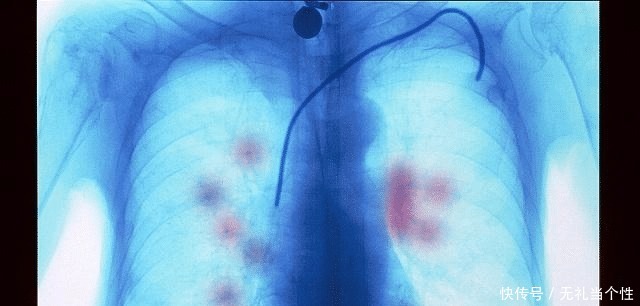

弄清楚什么病情?癌症不都是一样的,反正都治不好。你看,这种观念会害死人。首先要弄清楚,到底是什么癌症,什么病理类型,比如,肺癌,你不能简单地只是因为CT发现肺部长了肿块,报告说肺癌可能,你就开始安排后事了。这显然不对,你得进一步检查,得活检或手术,取得病灶组织进行病理检查,才能确诊是不是肺癌,是哪种肺癌,小细胞肺癌,还是非小细胞肺癌,而非小细胞肺癌还有腺癌,鳞癌,大细胞癌等,这都必须明确。还要进行基因检测,弄清楚基因突变情况。很多人所谓的癌症,其实并没有确诊,也没有弄清楚确切的病理类型。

其次,要弄清楚分期。不同的癌症不一样,同样的癌症,不同的分期了不一样,早期多数有机会治好,你不弄清楚分期,就说放弃治疗?即便是晚期,也有不同情况,有的晚期癌症也仍有治愈可能,有的尽管不能治愈,但可能较长期带癌生存,当然,也有的没有有效的治疗手段。所以,你得弄清楚分期啊。【 分期|假如你不幸患上“癌症”,你会怎么办是治疗还是放弃!】